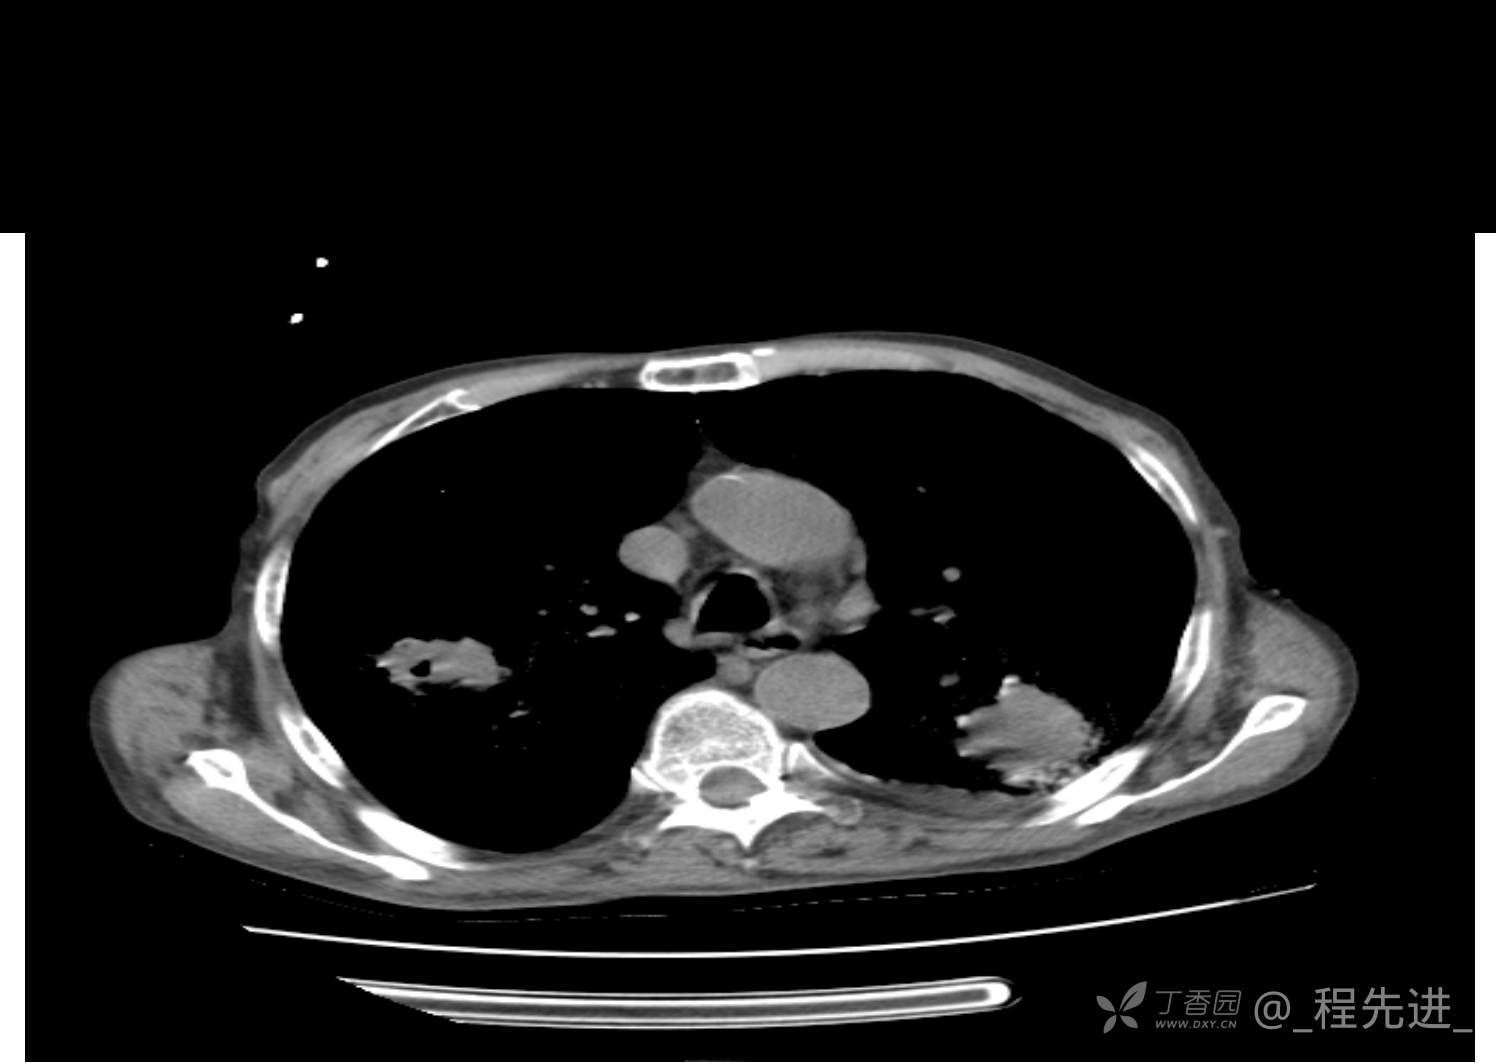

患者性别:男

患者年龄:81岁

简要病史:反复咳嗽、咳痰20余年,加重1周。两肺呼吸音低,可闻及散在干湿啰音。